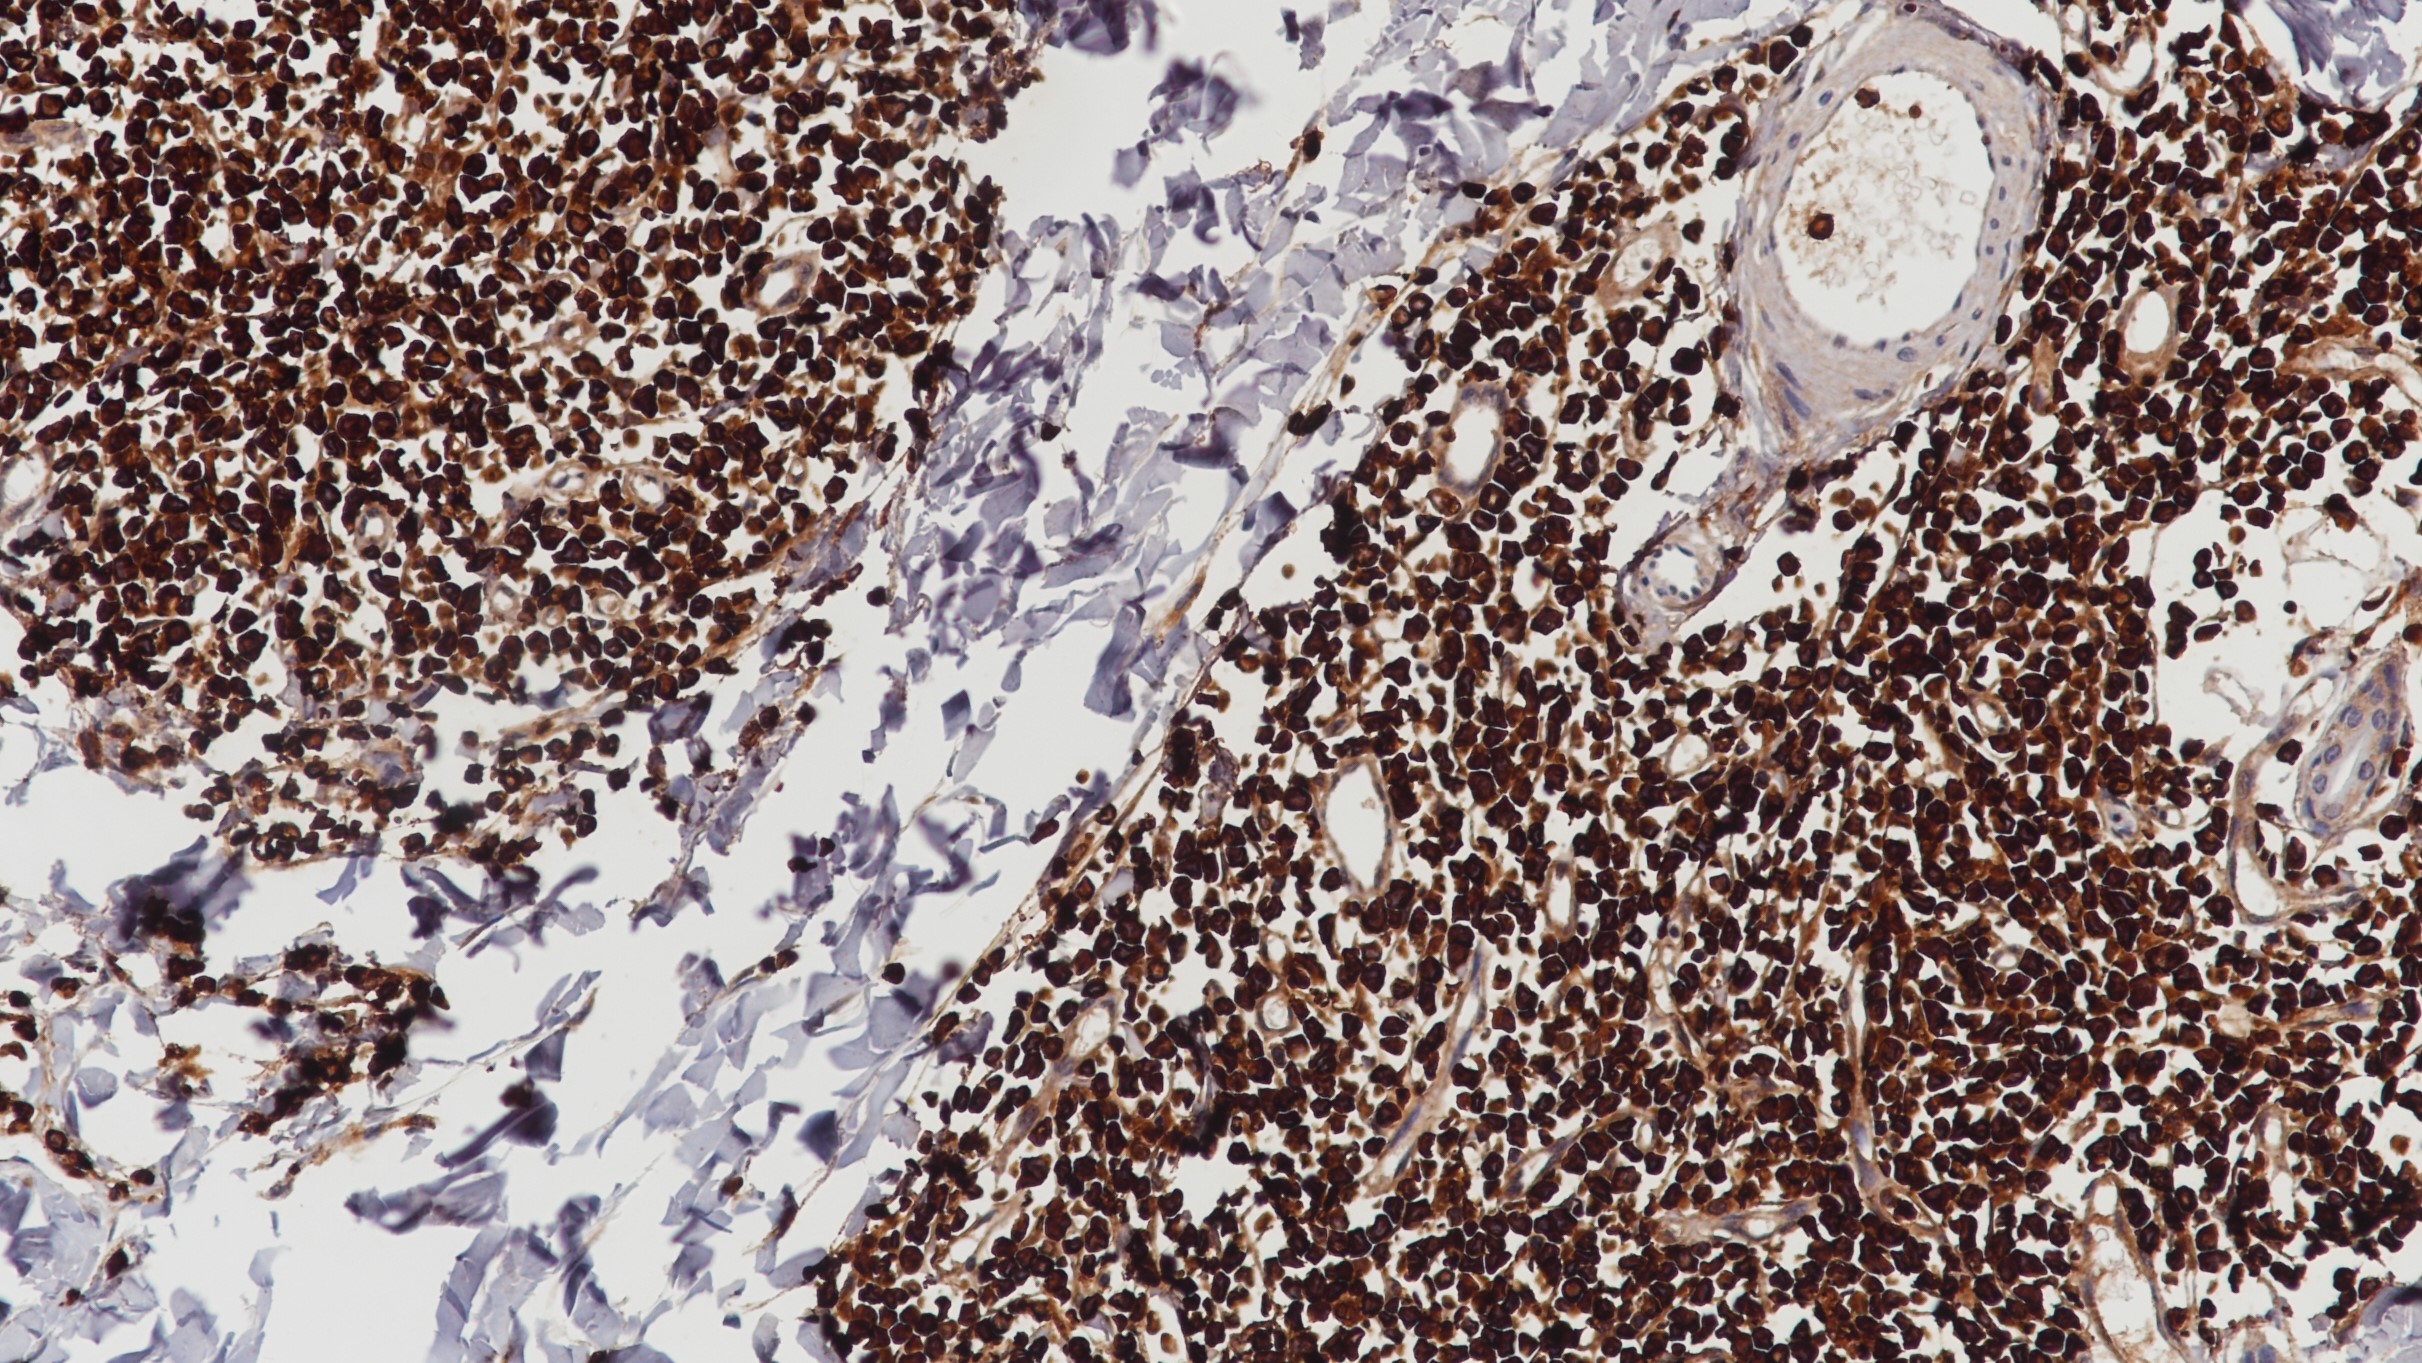

Villin是一种分子量约为93kDa的钙调肌动蛋白,主要与调节肌纤维聚集活动相关。它是肠道和肾小管上皮细胞的刷状缘微绒毛的主要组成成分。在正常组织中,Villin只在胃肠道以及泌尿道的上皮中表达。在肿瘤组织中,Villin在大肠癌、肝细胞癌、子宫内膜癌、卵巢癌和肺癌中均有表达。Villin通常被用于鉴别直肠转移癌与其他胃肠道原发癌。

阳性对照

结肠